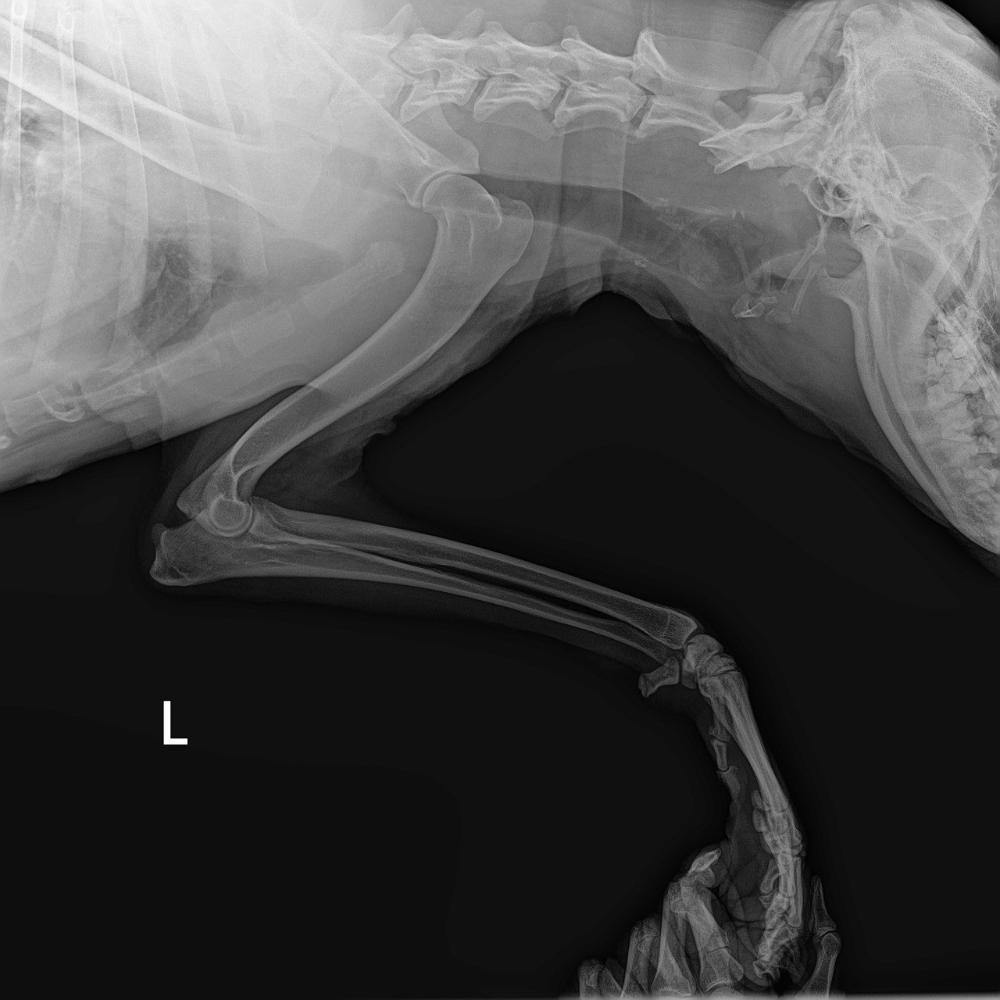

Нечаева и Ко Опубликовано 16 декабря, 2025 Опубликовано 16 декабря, 2025 (изменено) Наши новости. Господи, что ни день, то сюрпризы😥 Изменено 16 декабря, 2025 пользователем Нечаева и Ко 1 4